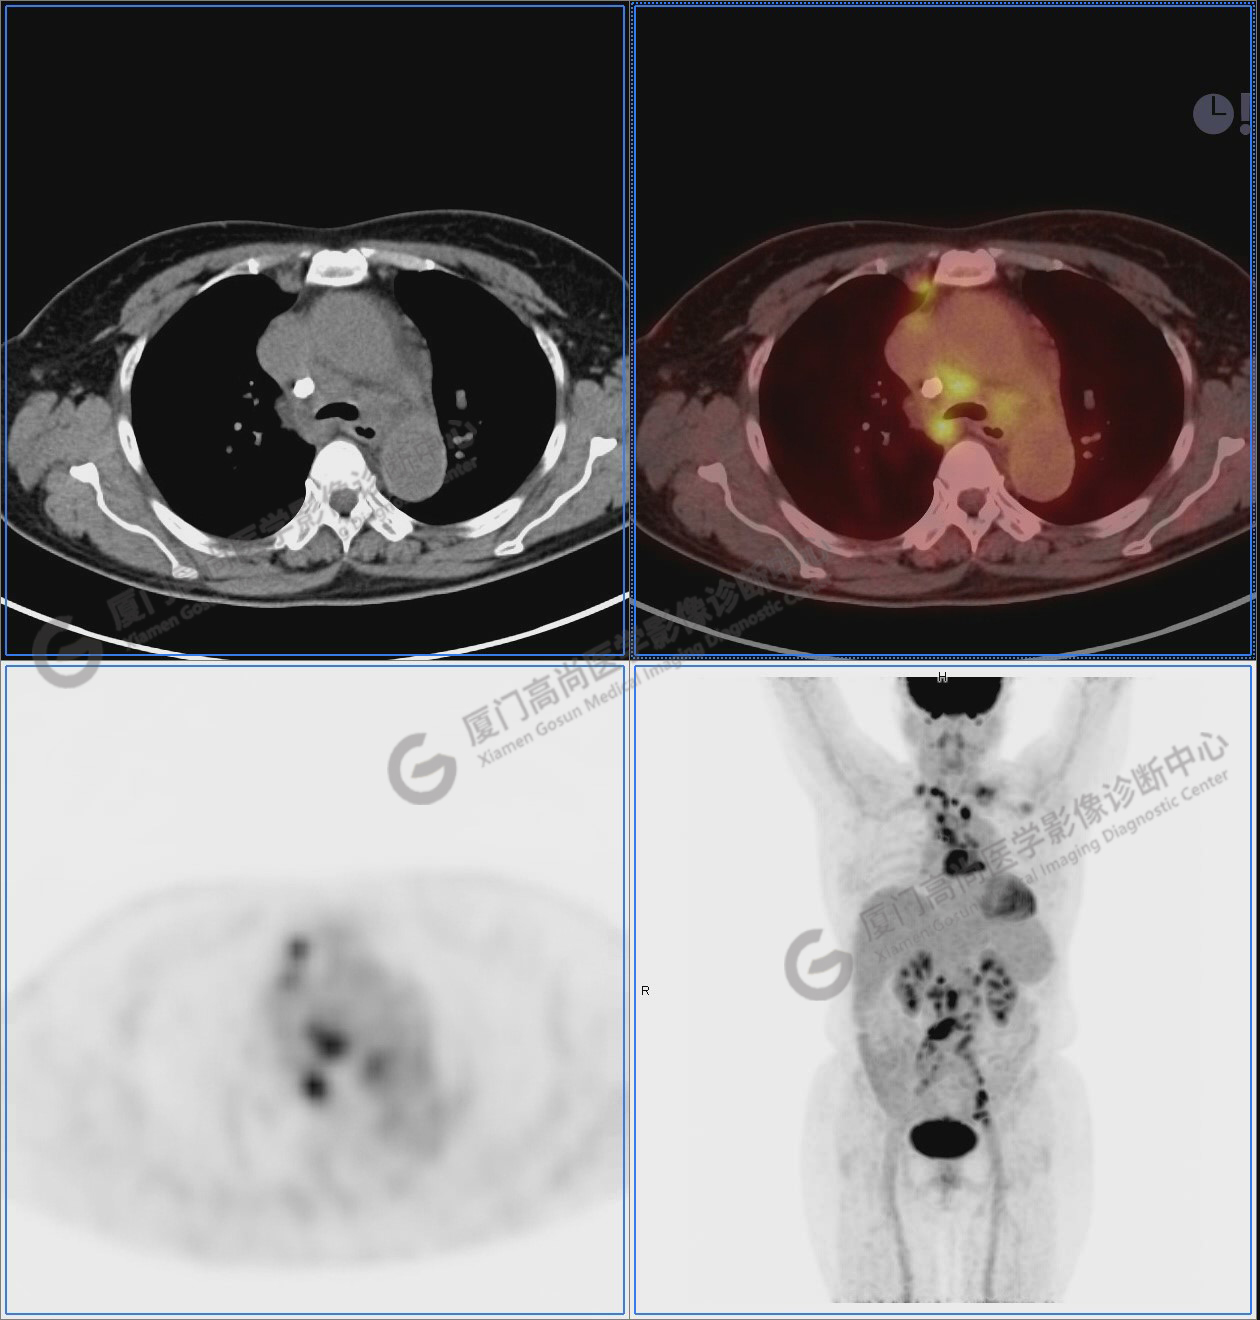

圖1:PET/CT全身圖像

圖2-9:雙側(cè)鎖骨區(qū)、縱隔、右側(cè)內(nèi)乳區(qū)、腸系膜緣、腹膜后、雙側(cè)髂血管旁及盆腔多發(fā)腫大淋巴結(jié)影,代謝不同程度增高,考慮為轉(zhuǎn)移。

圖3